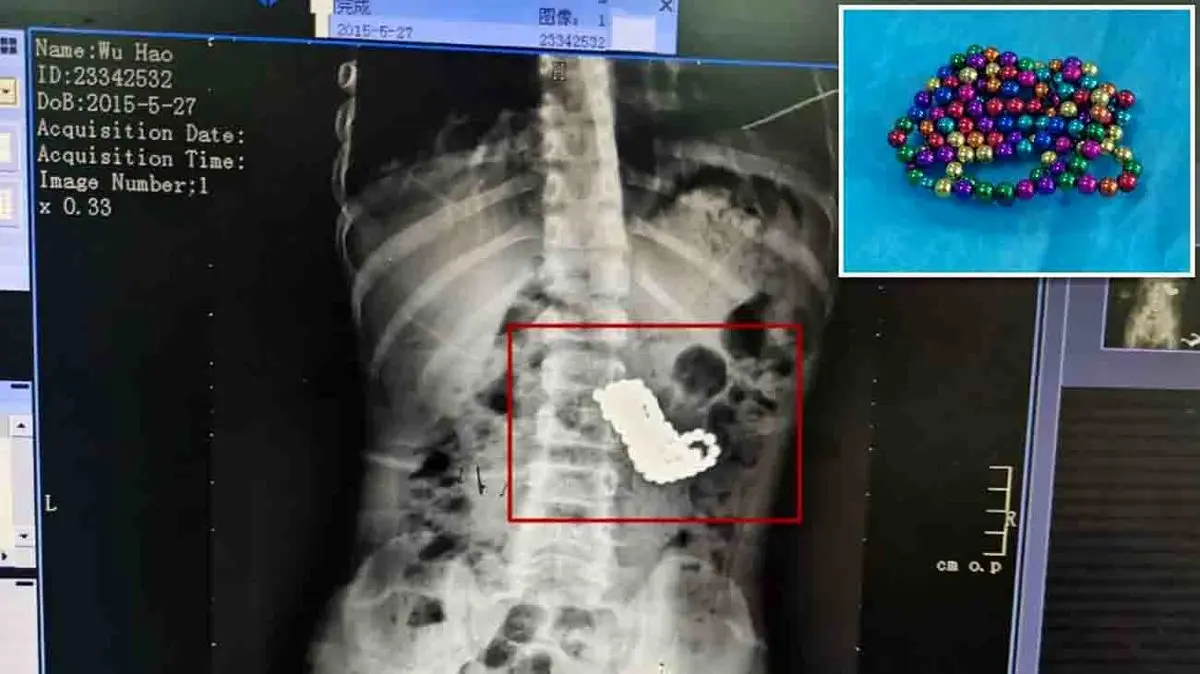

پزشکان پس از شنیدن شرح ماجرا و انجام اسکن ایکس ری، بیش از صد توپ را در شکم این کودک مشاهده کردند. این کودک بلافاصله تحت عمل جراحی اورژانسی قرار گرفت و جراحان در یک عمل جراحی ۴ ساعته تمام توپها را از شکم او خارج کردند. در تصاویر منتشره توپهای مغناطیسی که از شکم کودک خارج شده است دیده میشود.